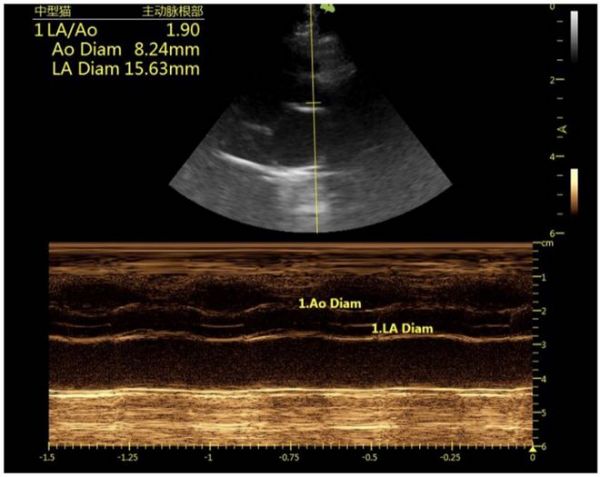

图4:右侧长轴四腔心 图5:右侧长轴四腔心

图6:右侧长轴五腔心

9.1 心脏超声结果分析

心超M-mode可见左心室舒张末期室中隔厚度约6.8mm,左室壁厚度约:7.8mm,均超过6 mm,提示肥厚性心肌病;左心房与主动脉内径比值约1.9(正常<1.5),提示左心房扩张,左心前负荷升高,有比较高的肺水肿风险。另外房间隔处存在左向右分流,存在房间隔缺损的情况,同时在心脏周围可见少量游离液性暗区,提示存在胸腔积液。